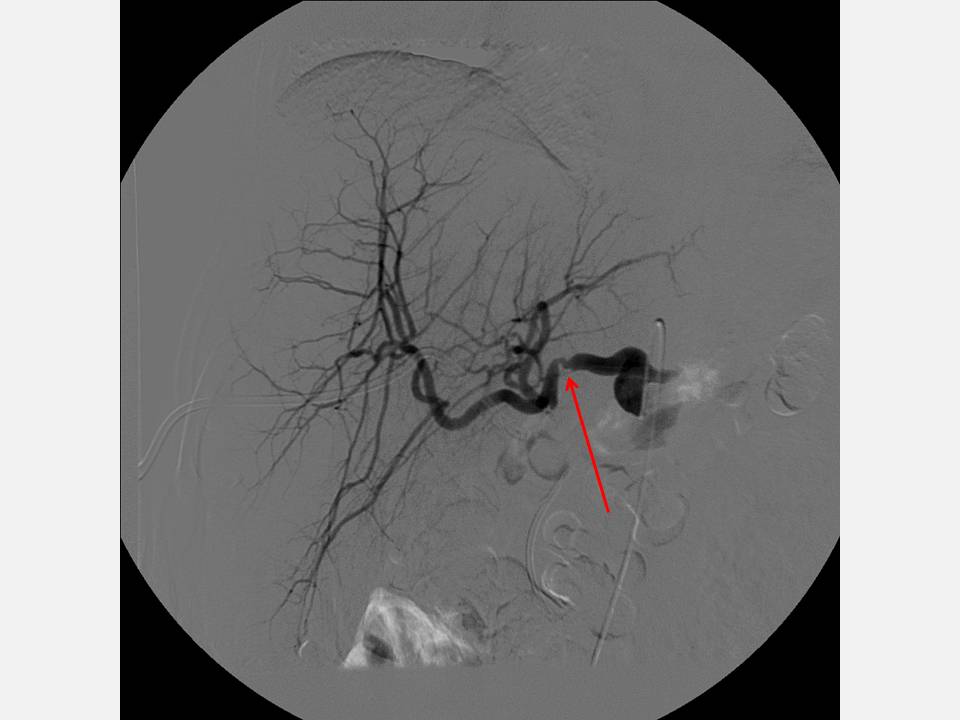

The Pump and the Tubes Hepatic Artery Complications Following Liver Transplant Arterial Conduit Liver Transplant although aortohepatic conduits (ahcs) provide an effective technique for arterialization in liver transplantation (lt). Arterial conduits (ac) in liver transplantation (lt) offer an effective rescue option when regular arterial graft revascularization is not. the use of an arterial conduit is an accepted alternative to the utilisation of native recipient hepatic artery for specific. the successful outcome in. Arterial Conduit Liver Transplant.

The Pump and the Tubes Hepatic Artery Complications Following Liver Transplant Arterial Conduit Liver Transplant although aortohepatic conduits (ahcs) provide an effective technique for arteriali‐zation in liver transplantation (lt). the successful outcome in orthotopic liver transplantation (olt) is critically dependent on the uncompromised hepatic graft blood. Arterial conduits (ac) in liver transplantation (lt) offer an effective rescue option when regular. although aortohepatic conduits (ahcs) provide an effective technique for arterialization in liver. Arterial Conduit Liver Transplant.

The Pump and the Tubes Hepatic Artery Complications Following Liver Transplant Arterial Conduit Liver Transplant Arterial conduits (ac) in liver transplantation (lt) offer an effective rescue option when regular arterial graft revascularization is not. Arterial conduits (ac) in liver transplantation (lt) offer an effective rescue option when regular. The successful outcome in orthotopic liver transplantation (olt) is critically dependent, among other. arterial conduits (ac) in liver transplantation (lt) offer an effective rescue option when. Arterial Conduit Liver Transplant.